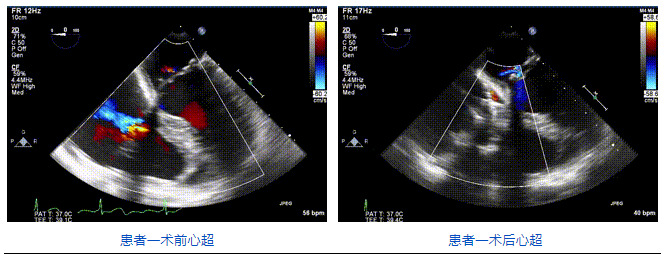

2021年12月24日,復(fù)旦大學(xué)附屬中山醫(yī)院葛均波院士團(tuán)隊(duì)成功應(yīng)用LuX-Valve Plus為一例極重度三尖瓣反流(TR)合并房顫、房缺的患者完成了經(jīng)血管三尖瓣置換術(shù),這是在前基礎(chǔ)上,本周完成的第三例經(jīng)血管三尖瓣置換手術(shù),葛均波院士、周達(dá)新教授等與心外科魏來教授、賴顥教授,心超室的潘翠珍教授、李偉教授及麻醉科的郭克芳教授共同完成了本周手術(shù),均獲得圓滿成功!患者術(shù)后超聲顯示無TR,臨床癥狀明顯改善。本周手術(shù)的成功也為L(zhǎng)uX-Valve Plus救治性臨床研究添上了濃墨重彩的一筆。

三例患者入院后,葛均波院士團(tuán)隊(duì)周達(dá)新教授、潘文志教授、張?jiān)床┦俊㈥惿┦考靶某业呐舜湔浣淌凇⒗顐ソ淌趯?duì)患者的情況進(jìn)行詳細(xì)評(píng)估和討論,最終決定為三例患者選擇LuX-Valve Plus40mm、50mm和50mm型號(hào)的瓣膜進(jìn)行手術(shù)治療。手術(shù)后即刻拔除氣管插管,術(shù)后患者三尖瓣反流癥狀得到顯著改善,復(fù)查心超結(jié)果顯示人工三尖瓣瓣膜支架固定穩(wěn)定,瓣葉關(guān)閉形態(tài)未見異常,未見明顯反流。